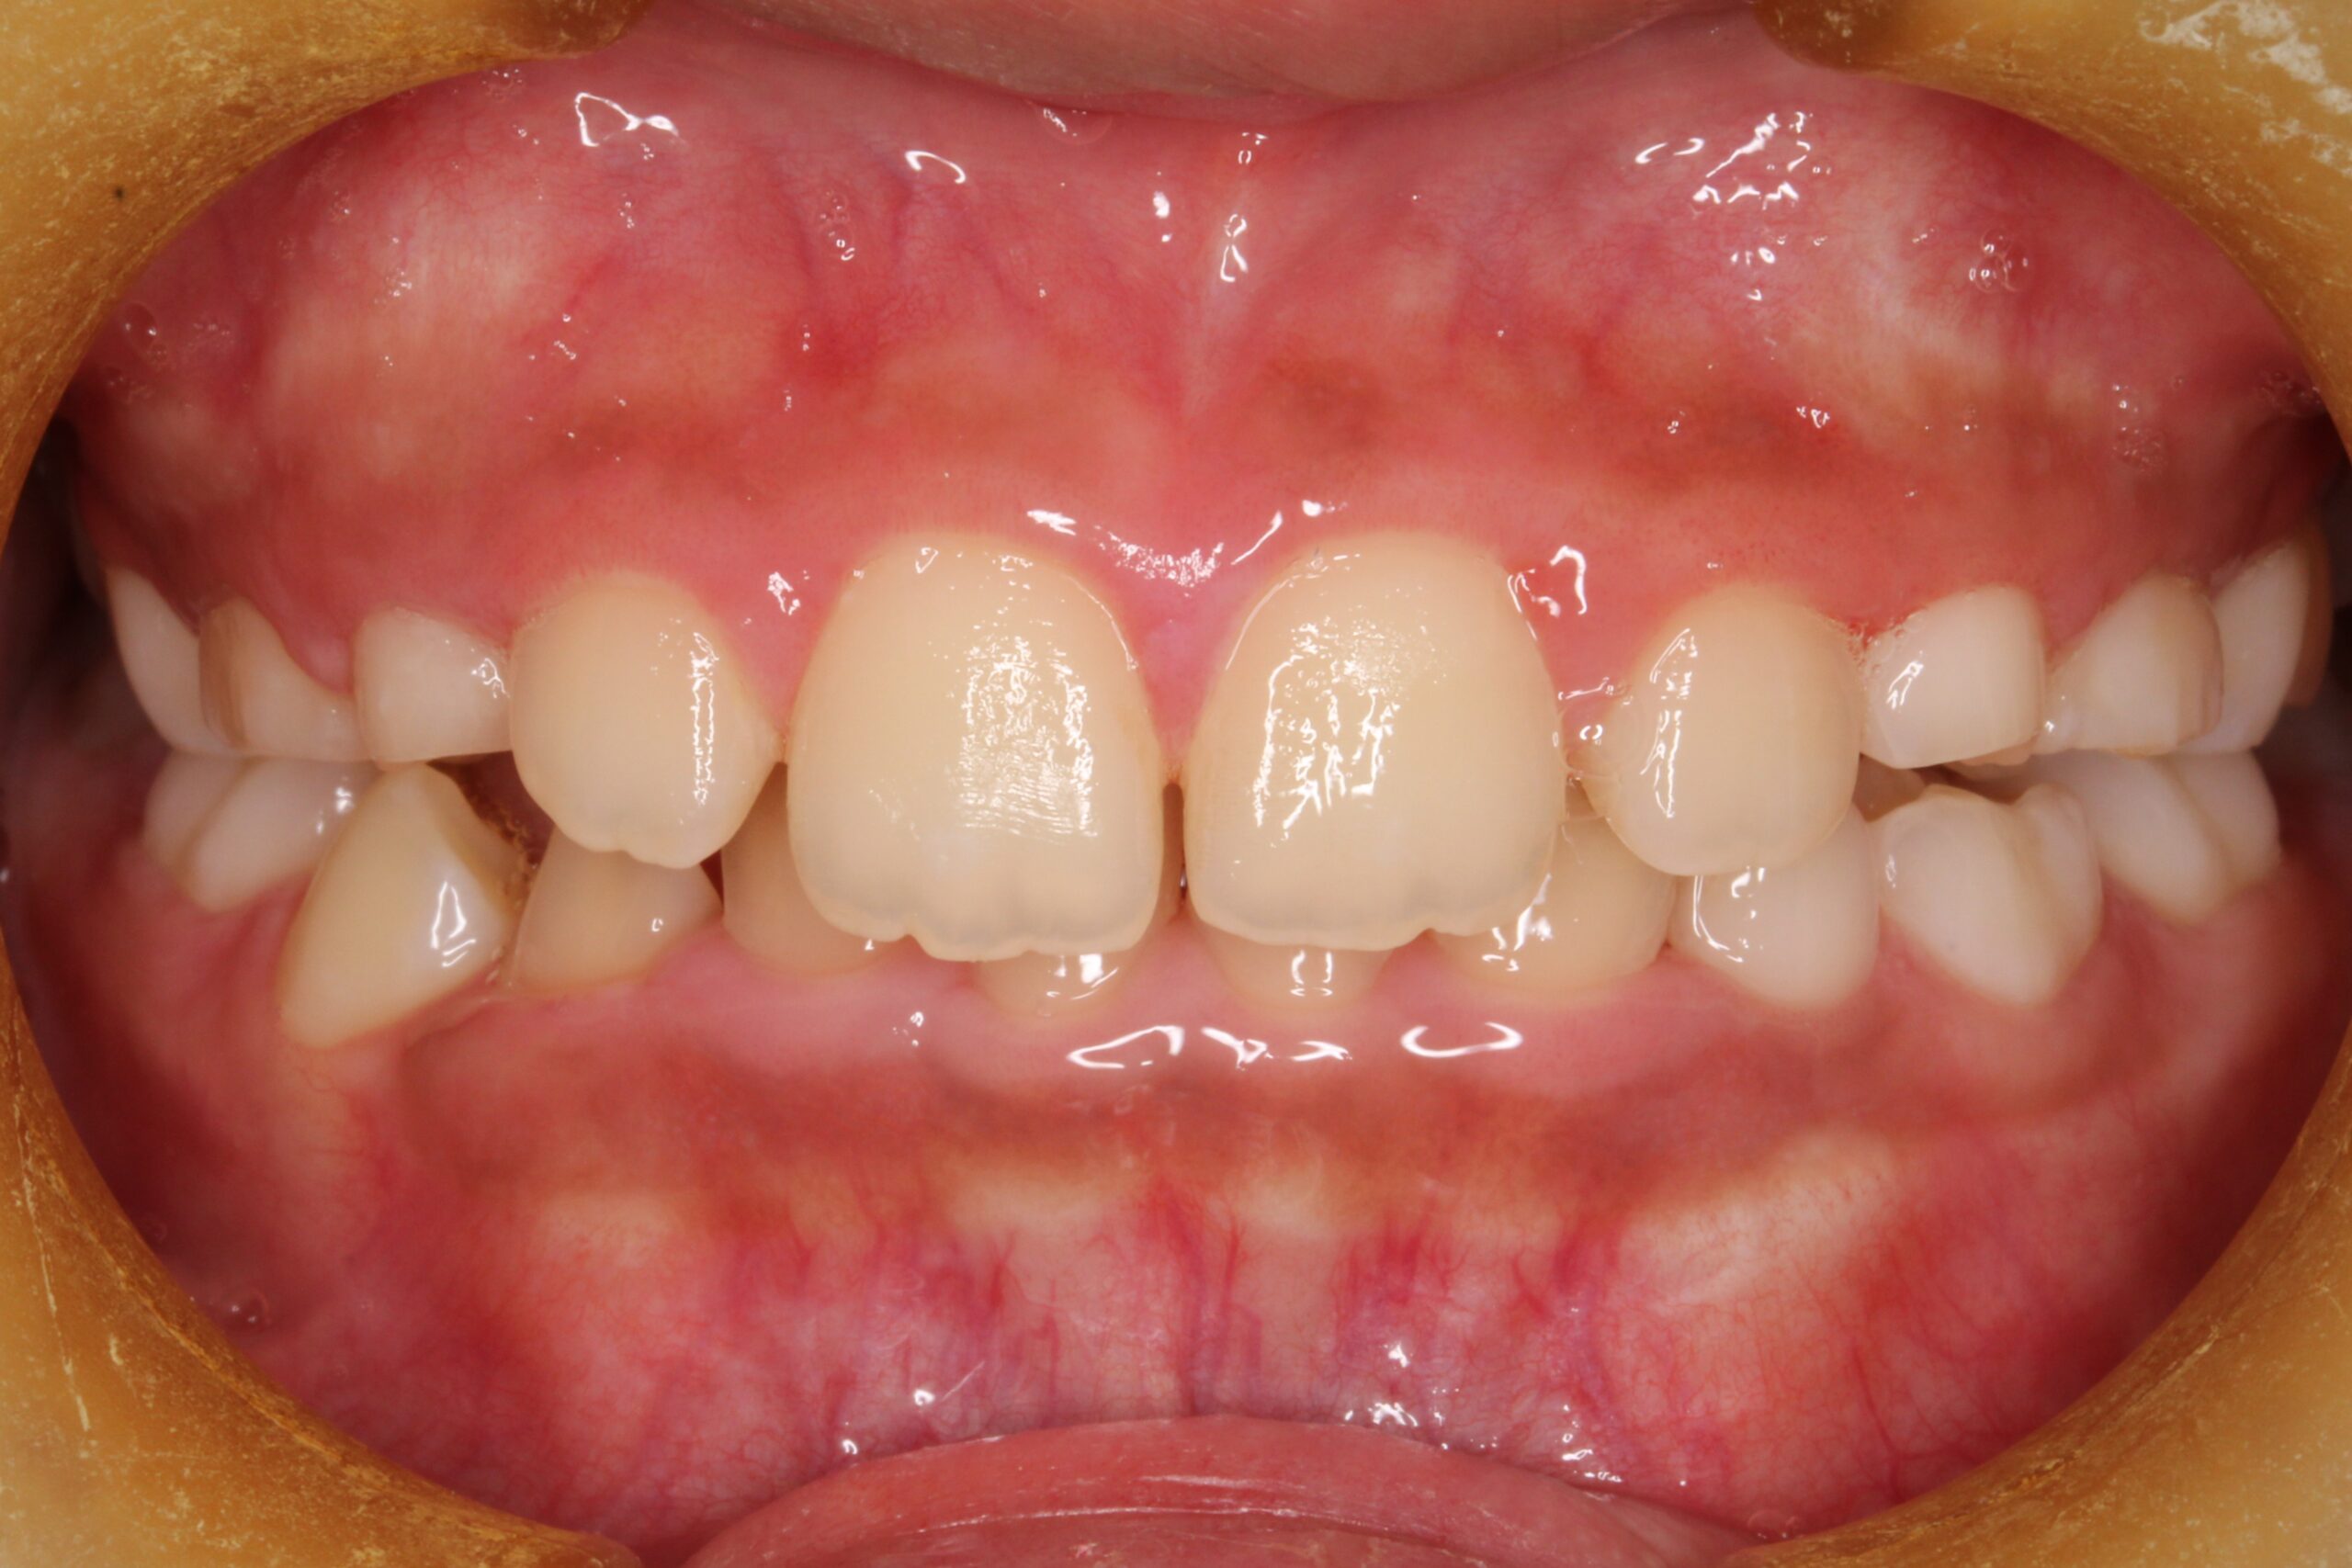

矯正術後:正面

矯正術前:右側